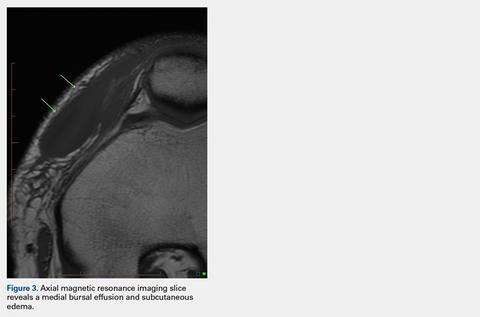

An acutely marginated, 1.5 cm × 3 cm, longitudinal and transverse fluid defect “crevasse” was identified at the midline in the prepatellar subcutaneous fat overlying the distal quadriceps tendon and corresponded to a clinically palpable abnormality (Figures 1, 2).

These findings were consistent with a localized “fat fracture.” There was an associated, 2 cm × 6 cm, sagittal and coronal/longitudinal, medial prepatellar bursal fluid complex and subcutaneous edema adjacent to the fat fracture (Figure 3). However, the patellar and quadriceps tendons were intact. A 12-mm focus of marrow edema at the superior pole of the patella was consistent with a contusion.